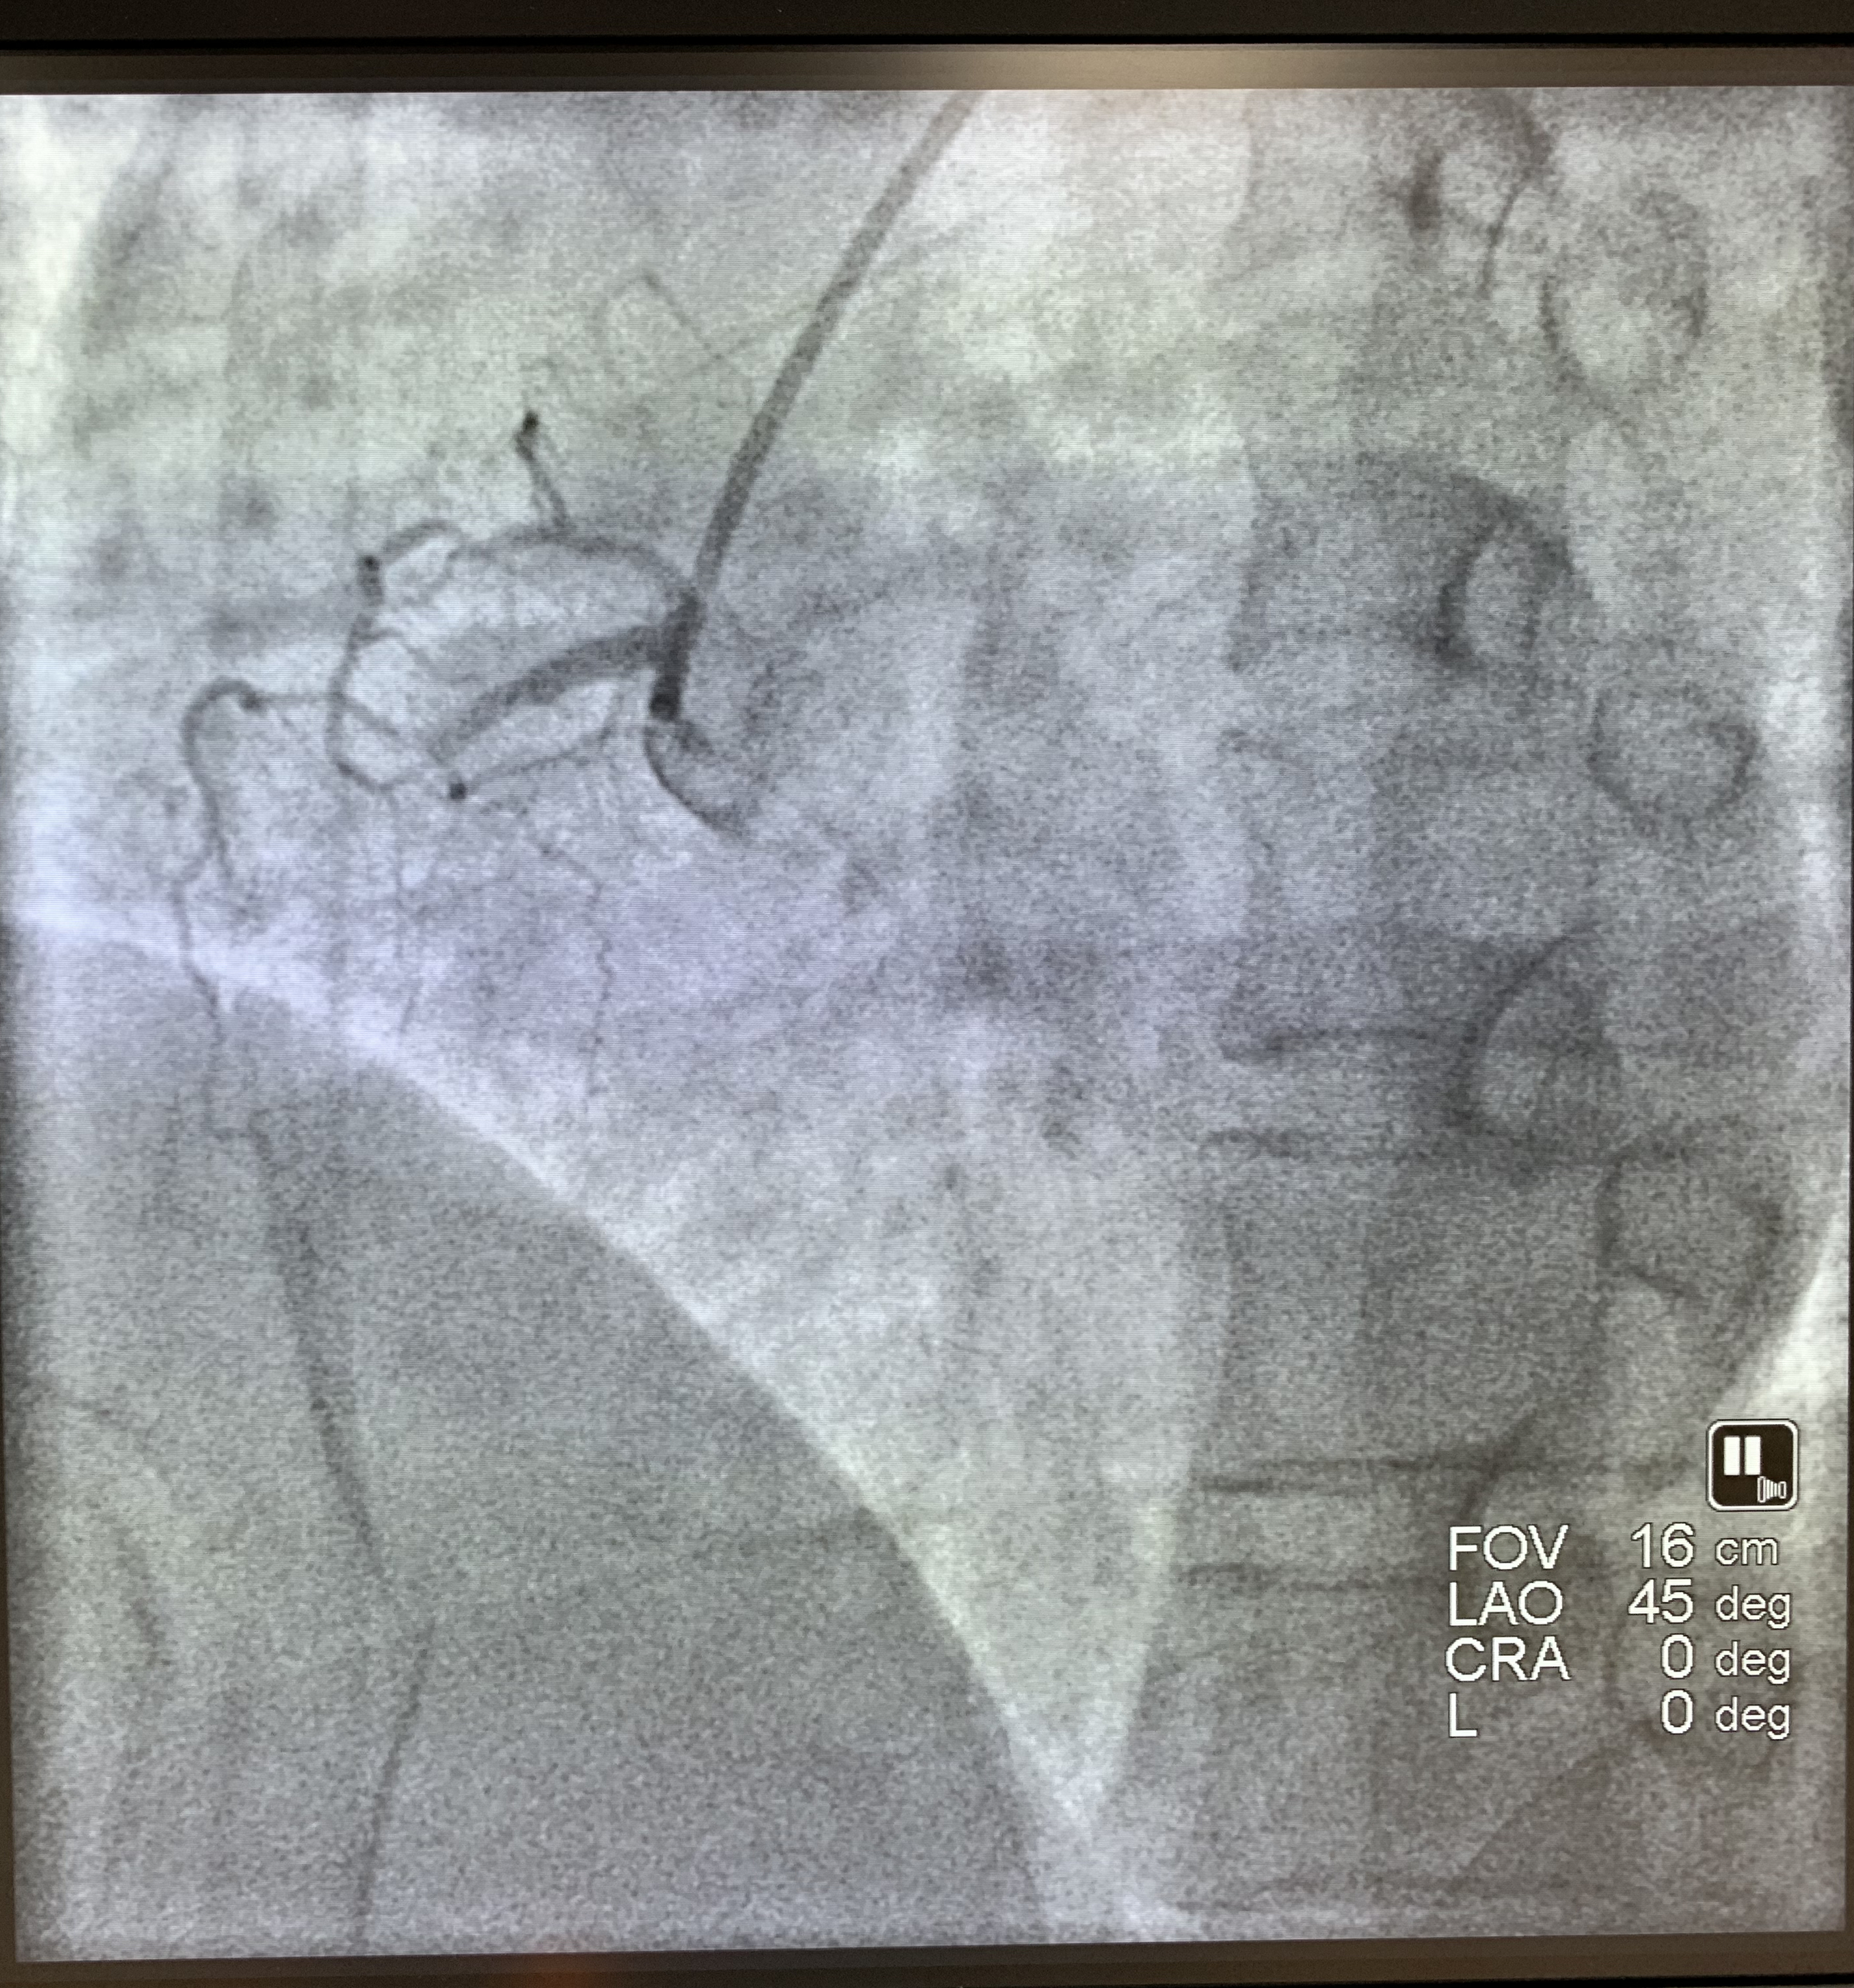

术前

马王堆院区急救。经过心电图等相关检查,迅速明确诊断其为急性心肌梗死,需立即进行急诊介入手术。在冠脉造影检查过程中,医生发现患者的右冠近段以远闭塞。术中,通过用血栓抽吸装置,将冠脉内血栓抽出,然后成功放入一枚支架。术后,患者胸痛不适的感觉明显缓解。